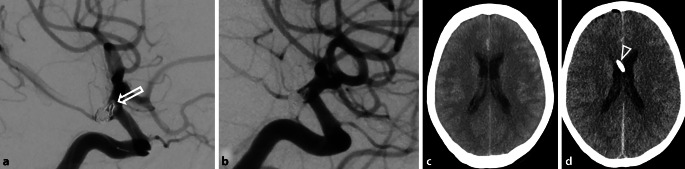

背景:蒂罗非班可用于治疗动脉瘤血栓栓塞并发症,也可用于动脉瘤治疗范围内所需的急性支架植入或血流分流器植入。我们旨在研究替罗非班在这类患者中的疗效和安全性:我们对 2009 年至 2019 年期间在我院接受动脉瘤治疗并接受围介入期替罗非班给药的所有患者进行了回顾性分析:共纳入 105 名患者,其中女性占 61%,男性占 39%(平均年龄 = 53 岁,IQR:44-60 岁)。67名患者接受了动脉瘤急诊治疗,38名患者接受了择期治疗。在接受急诊治疗的患者中,22%(15/67)发生了出血事件,7.46%(5/67)出现了症状。接受选择性动脉瘤治疗的患者没有发生出血事件(P = 0.002)。在35名需要脑室外引流管(EVD)的患者中,22.86%(8/35)的患者出现了与EVD相关的出血,但无一出现症状(p = 0.007)。在5名需要开颅手术的患者中,2人出现了严重出血,1人出现了非严重的开颅手术相关出血(p = 0.20):结论:在动脉瘤治疗的围介入并发症或紧急支架植入术中使用替罗非班可能是安全的。结论:在动脉瘤治疗的围介入并发症或急诊支架治疗中使用替罗非班可能是安全的,但在需要进行开颅手术时必须谨慎。在选择性动脉瘤治疗中,针对围手术期并发症使用替罗非班似乎是安全的。

Results: A total of 105 patients were included, with 61% women and 39% men (mean age = 53 years, IQR: 44-60 years). Sixty-seven patients underwent emergency aneurysm treatment, and thirty-eight were treated electively. Hemorrhagic events occurred in 22% (15/67) of the patients treated acutely, with 7.46% (5/67) exhibiting symptoms. Patients undergoing elective aneurysm treatment experienced no hemorrhagic events (p = 0.002). Among the 35 patients who required an external ventricular drain (EVD), 22.86% (8/35) developed EVD-related hemorrhages; however, none were symptomatic (p = 0.007). Of the five patients who required a craniotomy, two experienced significant bleeding, and one experienced non-significant craniotomy-related bleeding (p = 0.20).